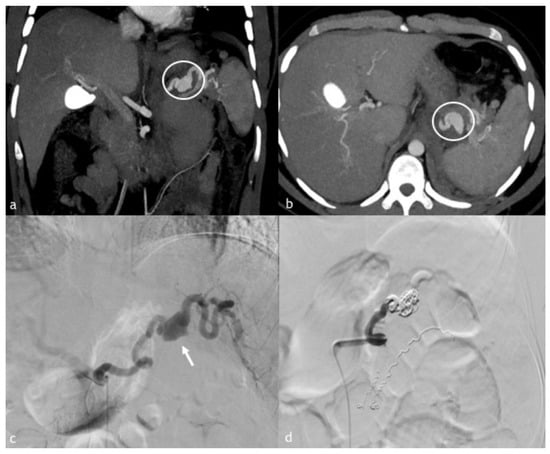

Figure 2. (ad). A 20-year-old man presented to our emergency department after high blunt trauma. (a,b) Axial and coronal MPR reconstruction images demonstrate splenic artery PSA, rounded by coarse hematoma (circle). (c) Digital subtraction angiography of splenic artery demonstrates PSA (arrow) with the presence of multiple wall irregularities, such as blebs (a warning sign of an impending breakout). (d) Post-embolization angiographic control with complete embolization of the splenic artery. There are also other coils due to another adrenal hemorrhage, successfully treated in the same session.